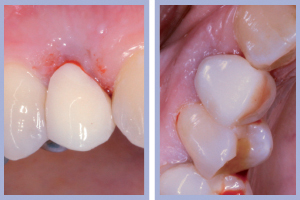

- Figg. 27a, b – Consegna dei manufatti

- Figg. 28a, b – Confronto tra inizio e fine trattamento

- Figg. 29a, b Manufatti di destra e radiografia di controllo. Si noti l’ottima integrazione tissutale

- Figg. 30a, b – Manufatti di sinistra e radiografia di controllo